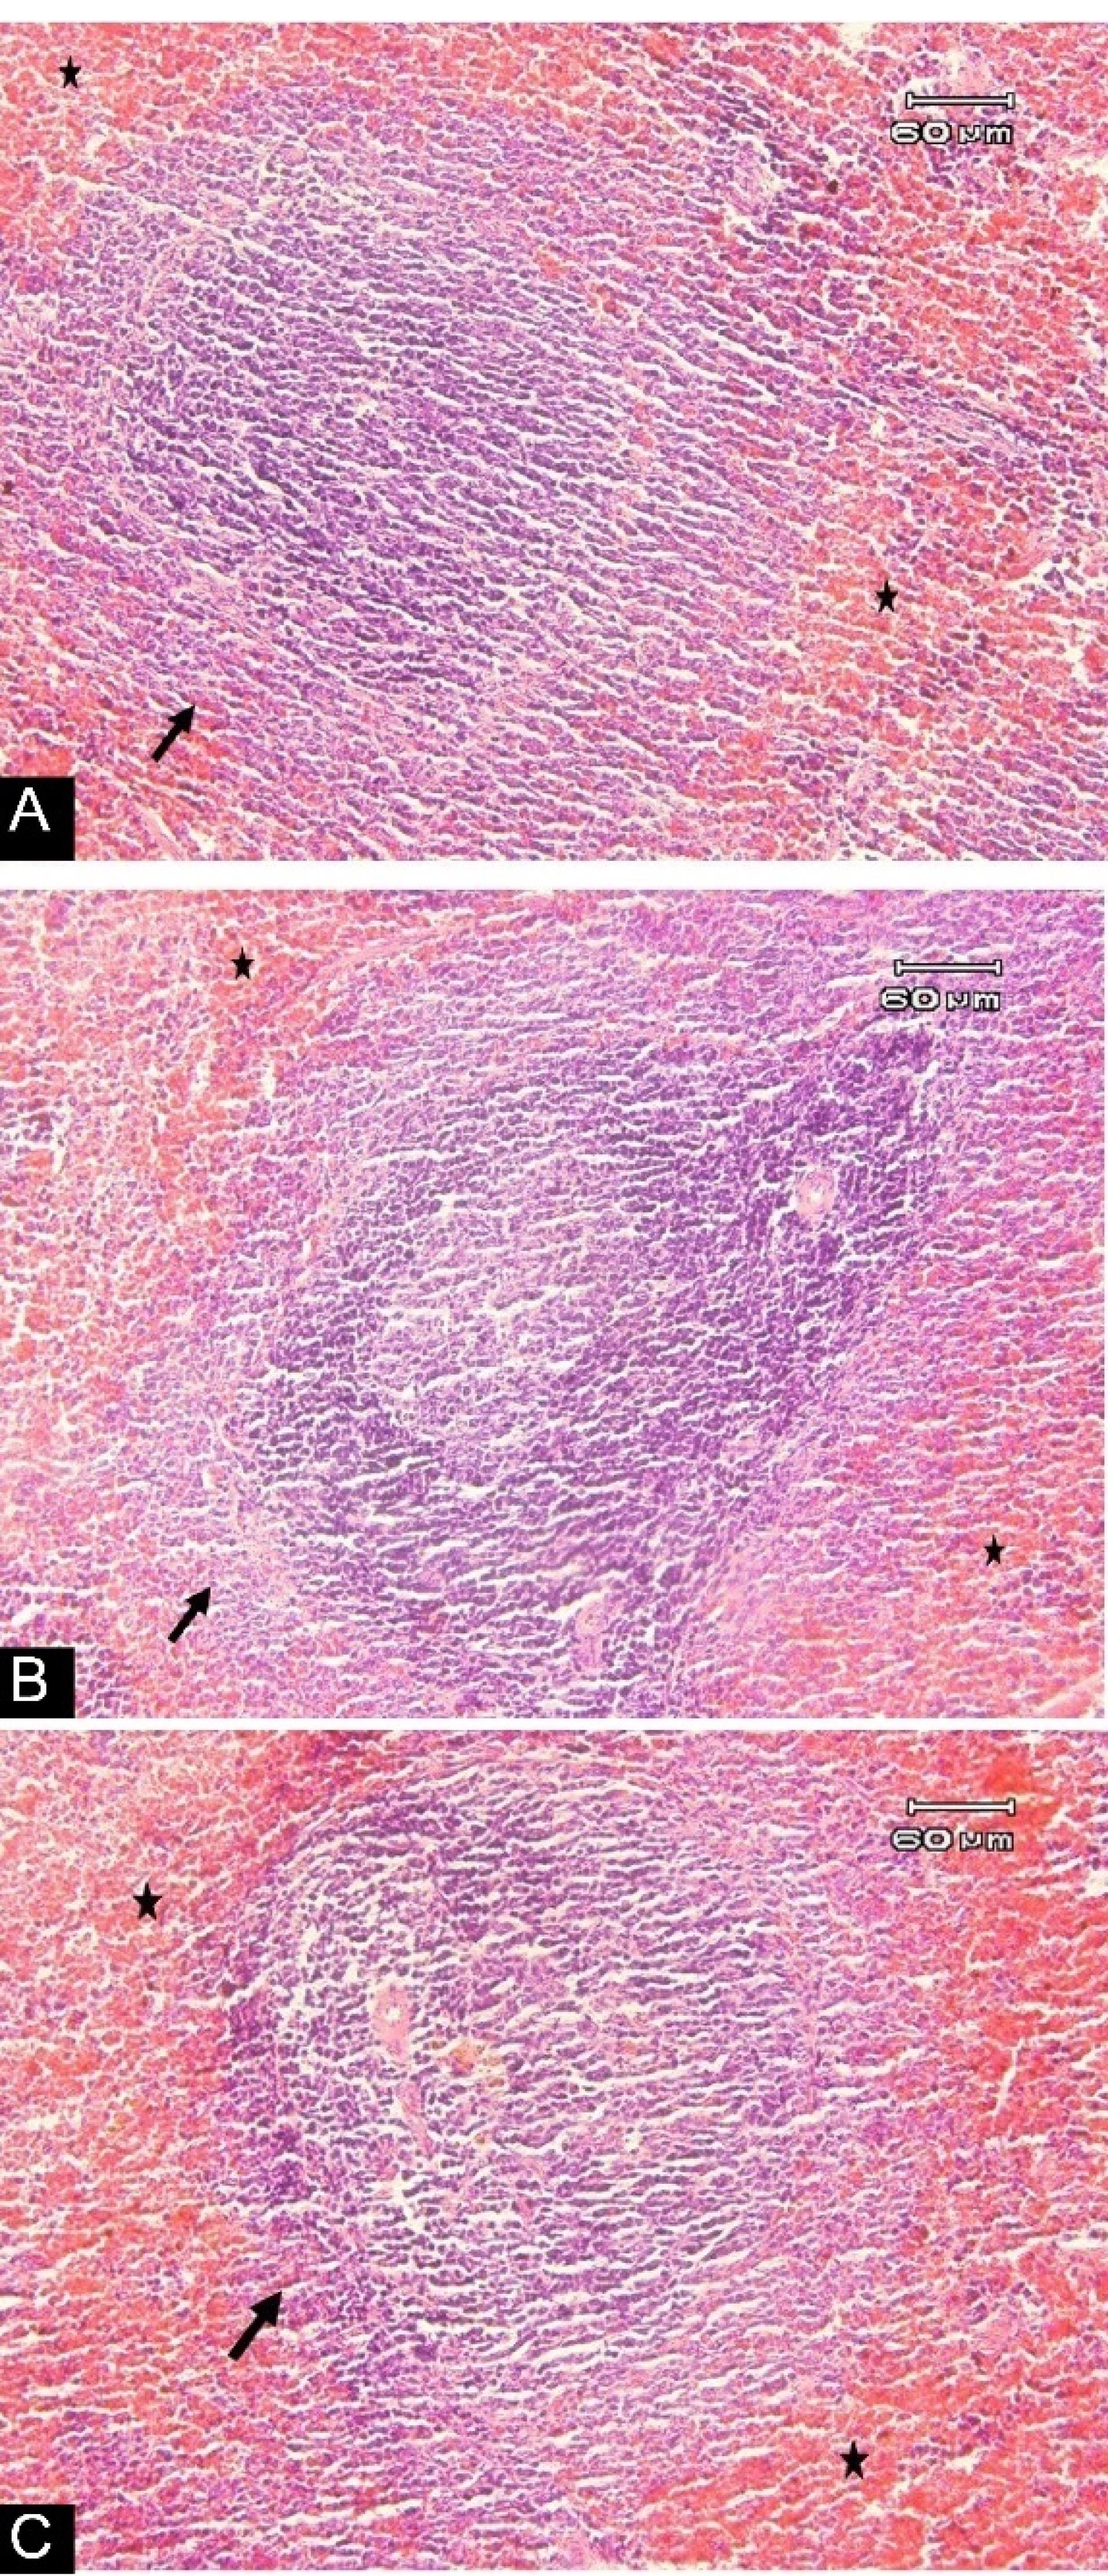

Photomicrographs of the Spleen Tissue of Rats Stained with H & E: (A) Standard diet rats, showing the natural structure of lymphoid follicle (arrow), with mild congestion (stars) of spleen tissue. (B) Non-GM diet for 90 days, denoting the natural structure of lymphoid follicle (arrow), with mild congestion (stars) of spleen tissue. (C) GM diet for 90 days, displaying the natural structure of lymphoid follicle (arrow), with mild congestion (stars) of spleen tissue. (magnification: 100 × ). Note. GM: Genetically modified

Changes in body weight and food intake are presented in Figures 1 and 2, respectively, with no significant changes in weight or food intake. The absolute mean organ weights are illustrated in Table 2. The results indicated no significant differences in organ weights of rats in all groups. However, the spleen weight was higher compared to other study groups. Moreover, the findings of the hematologic assessment of treatment groups are presented in Table 3, showing no statistically significant difference in hematologic parameters among treatment groups. Only, hemoglobin concentrations in the standard group were slightly higher than those in the other two groups (P < 0.001), while GM-fed rats tended to show lower levels of MCH, WBC, neutrophil, and lymphocyte compared to other treatment groups. In contrast, this group experienced a higher level of platelet compared to the other groups. Histologic derangements were observed in the pancreastissueof the GM soybean oil group. Various levels of destruction were also observed in this group, including severe congestion in the exocrine and endocrine section, the presence of inflammatory cells in the focal region of the exocrine (pancreatitis), vascular congestion, and a reduced number of Langerhans islands (Figure 3). In terms of changes in spleen tissue, no significant difference was observed between treatment groups except for slight congestion (Figure 4).

On the other hand, no histologic changes were reported in spleen tissue except for minor congestion in all three groups, generally occurring due to anesthesia in rats. Several studies reported no change in the spleen tissue of GM-fed animals. In a study by Lin et al,36 after feeding GM virus-resistant papaya fruit for 90 days in rats, no changes were observed in the spleen tissue. Similar results were also reported after GM-maize feeding.2 Several other studies also reported similar findings with no change in the spleen tissue of GM-fed animals.37-39 The possible reason is that immediate allergic induction in animals is extremely low.40 These valuable findings indicate that other animal studies confirming these results would elucidate the social and practical implications of GM foods. This issue will be directed towards the widespread consumption of GM foods in society by humans. However, the present study had some limitations, too. It seems that direct access to transgenic plants and their oil would provide better clarification about its effect. Furthermore, it seems that it is better to evaluate the long-term effects of GM foods; nevertheless, the current study just assessed the short-term effects of GM feeding.